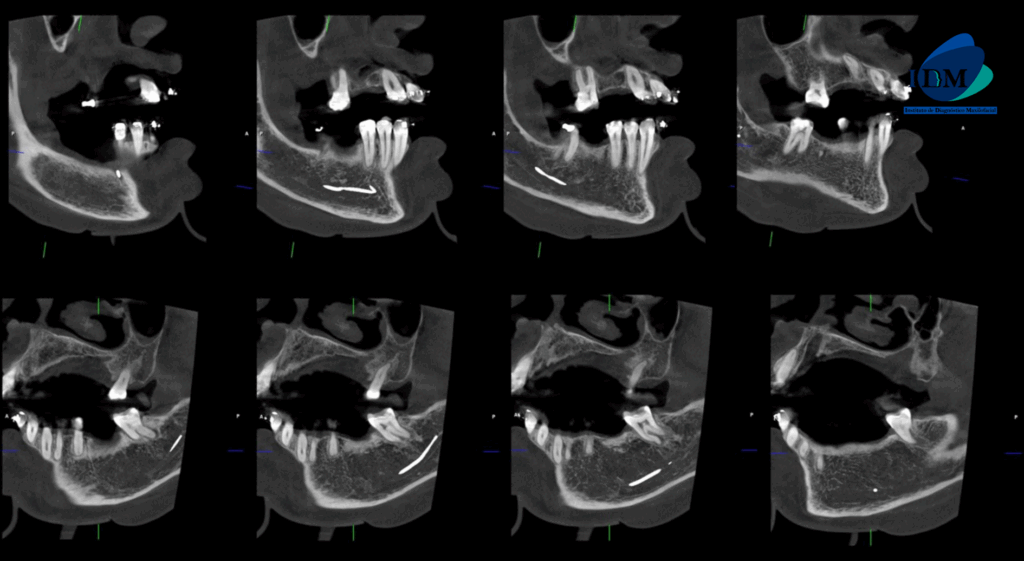

CORTES SAGITALES